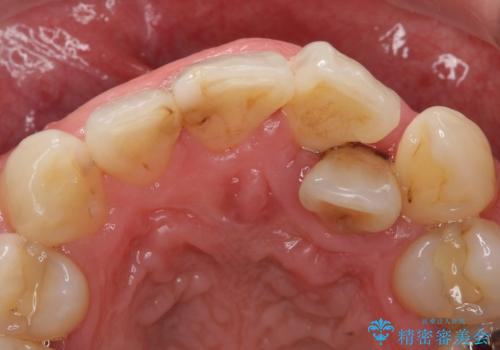

- 歯並びをきれいにしたい、歯を真っ白にしたいとのご希望により来院されました。

矯正治療とホワイトニングを提案しましたが希望されず、「接客関係の仕事で矯正治療は考えられない、短期間で治療を終わらせたい、ホワイトニングでは難しい位の人工的な白さにしたい」とのご要望により、治療前にワックスアップ模型を作製し何度もコンサルテーションを重ね、治療方針を決定しました。

歯頚ラインが変えられないことや天然歯を削るリスクをご理解頂いた上で、オールセラミッククラウンによる補綴治療を行いました。(見えない奥歯のみ天然歯のままとしました)

下の前歯1本だけ歯軸を変えるために神経をとり根管治療を行っております。

それ以外の歯は神経をとらずに済むよう、慎重かつ丁寧に歯の形態を整えました。

治療前に埋伏している親知らずの抜歯をおすすめしましたが、ご希望されませんでした。